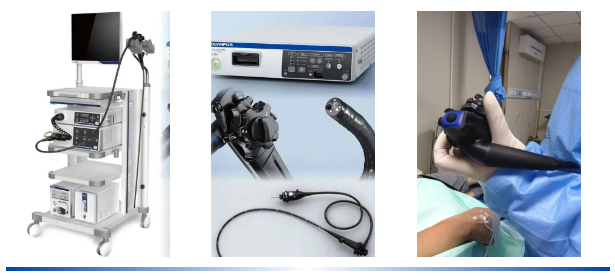

吕主任表示,像小张这样的案例并非个例。很多年轻人对消化道的轻微不适不以为意,觉得“忍忍就过去了”,殊不知一些看似普通的症状,可能是身体发出的健康警报。食管乳头状瘤虽然恶变概率相对较低,但如果长期忽视,也存在病变风险。而胃肠镜检查作为消化道疾病筛查的“金标准”,能够直接观察到食管、胃、肠道黏膜的细微变化,实现早发现、早诊断、早治疗。

“尤其是有消化道不适症状,比如反复腹痛、腹胀、反酸、排便习惯改变等,或者有消化道疾病家族史、长期存在不良生活习惯的人群,更应该重视定期筛查。”吕主任强调,“现在的无痛胃肠镜技术已经非常成熟,检查过程舒适,安全性高,不用有太多顾虑。”